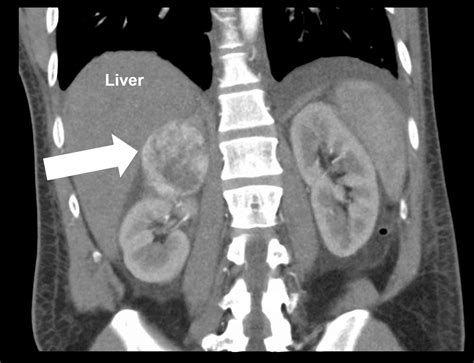

This imaging modality is highly sensitive and is considered the gold standard for evaluating adrenal masses. Whether your doctor suspects adrenocortical carcinoma, pheochromocytoma, or adrenal adenomas, this scan provides the structural data necessary to determine the size, shape, and density of the tissues in question.

• Evaluating an "incidentaloma"—a mass discovered unexpectedly during another unrelated medical exam.

• Distinguishing between benign (non-cancerous) growths and potentially malignant (cancerous) tumors.

Once the Adrenal CT Scan is complete, the images are sent to a radiologist. They analyze the "attenuation" or density of any detected masses. This is measured in Hounsfield units (HU). A low density (measured in low HU) typically suggests that a mass is a benign adenoma, which is very common. Conversely, higher density or irregular borders might prompt the medical team to conduct further investigations, such as follow-up blood work or specialized biopsies.